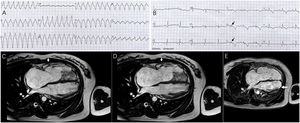

A previously healthy 25-year-old female presented to the emergency department with 5 h of palpitations and lightheadedness. Upon admission, the electrocardiogram (ECG) showed sustained ventricular tachycardia (VT) of left bundle branch block (LBBB) morphology with superior axis (Fig. 1A). The VT episode was terminated by intravenous amiodarone. Subsequent ECG after cardioversion revealed T wave inversion in all precordial leads and epsilon wave in leads V2 and V3 (Fig. 1B). Of note, her father died suddenly at the age of 38. Further cardiac magnetic resonance (CMR) revealed global hypokinesia in the free wall of the right ventricle (RV), as well as regional hypokinesia in the left ventricular apical wall (Fig. 1C, D, Supplement data Video 1). Notably, right ventricular ejection fraction was only 3%. Moreover, evidence of myocardial fibrosis was observed at the apex of the left ventricle (LV), with no such findings noted in the RV (Fig. 1E, Supplement data Video 2). Genetic testing revealed a mutation in the PKP2 gene. Based on the findings mentioned above, the diagnosis of arrhythmogenic right ventricular cardiomyopathy (ARVC) with LV involvement was established. The patient was started on metoprolol and was advised to undergo implantable cardioverter defibrillator (ICD) implantation.